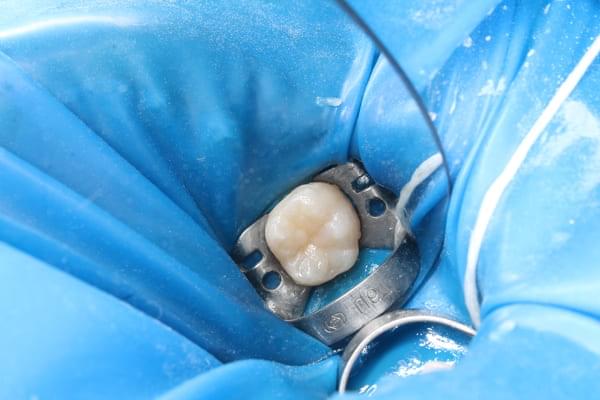

Поява перших постійних зубів, а це шості зуби, відбуваються, коли дитина ще не може, як слід провести їх гігієну та попіклуватись про їх здоров’я. Тому, на жаль вони і вражаються карієсом досить швидко. Пацієнт ще маленький – 6 років, а лікування потребує дорослого: зі знеболенням та ізоляцією. Саме таке і було проведене в даному випадку: зуб очищений від інфікованих тканин, відновлений фотополімерним матеріалом і готовий довго служити юному господарю.